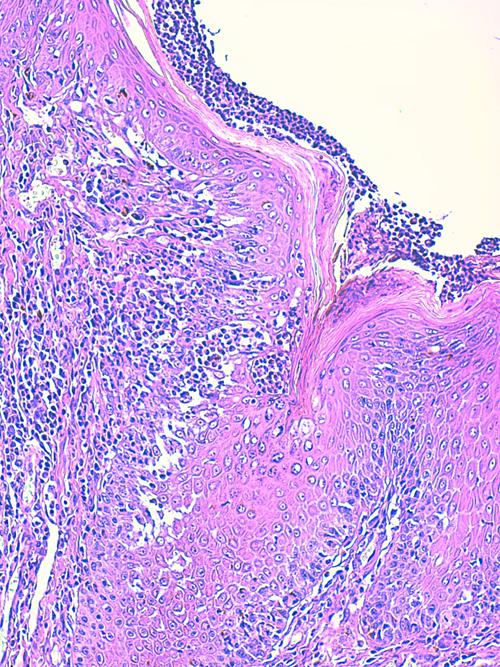

On observe une hyperplasie de l’épiderme et de la gaine épithéliale folliculaire externe en région infundibulaire, hyperplasie irrégulière associée à une alternance d’ortho et de parakératose. Les abouchements folliculaires sont dilatés, obstrués d’un matériel kératosique et pustulo-croûteux, les pustules étant riches en éosinophiles (Photo 1,2,3,4,5,6). On peut observer, au sein de l’épiderme et des abouchements folliculaires, des lésions pustuleuses dessinant de petits trajets entourés de structures épithéliales fissurées avec rupture des desmosomes intercellulaires avec un aspect focalement nécrolytique (Photo 4,7,8,9,10,11,12).

Photo 1 (Hémalun Eosine X 40) peau velue: L’épiderme et les infundibula folliculaires

sont hyperplasiques et hyperkératosiques. Les infundibula folliculaires sont le siège de pustules luminales et

pariétales, avec des fissurations linéaires parallèles au grand axe des follicules.

Le derme montre un inflammation péri-vasculaire et folliculo-centrée à diffuse.

Légendes de la Photo 1 :

- Double flèche bleue pointillée : grand axe des infundibula folliculaires à gaine épithéliale hyperplasique

- Double flèche verte : derme

- Ovales jaunes : pustules dans la paroi des follicules pileux

- Flèches jaunes : fissures linéaires dans la paroi des follicules pileux qui sont parallèles au grand axe des infundibula folliculaires

- Étoiles vertes évidées : lumière d’un follicule pileux hyperkératosique occupée par de la kératine et couche cornée hyperkératosique

- Étoiles rouges pleines : infiltrat dermique périvasculaire, périannexiel à diffus

- Étoiles turquoises pleines : lumière de follicules pileux obstruée de débris inflammatoires